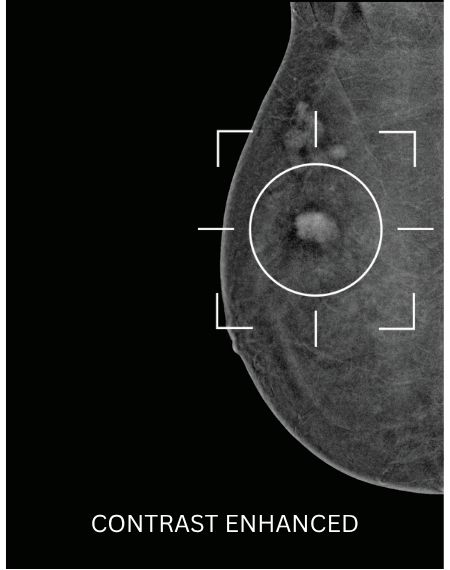

A Contrast Enhanced Mammogram (CEM) is similar to having a conventional mammogram but with the addition of a contrast enhancing IV dye containing iodine (the same dye as used in CT scans) to make it easier to characterise breast abnormalities and detect cancers that may not be visible in a standard mammogram. A doctor may refer you for a Contrast Enhanced Mammogram if you are at an increased risk of developing breast cancer, have dense breast tissue, or as an alternative to MRI.

Contrast Enhanced Mammography allows clinicians to see certain lesions and abnormalities that conventional mammography cannot detect – especially in patients at increased risk of breast cancer or who have dense breasts or implants.